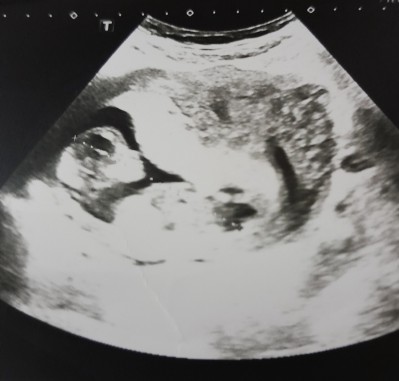

Size cinsiyet nedir doktor baktı ama birsey söylemedi emin olamadı galiba

Gebelik haftası 13+2